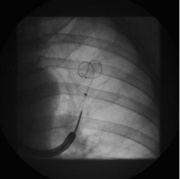

| 11:01, 7 במרץ 2015 | Bronchoscopic4.jpg (קובץ) |  |

20 קילו־בייטים | Motyk | 1 | |